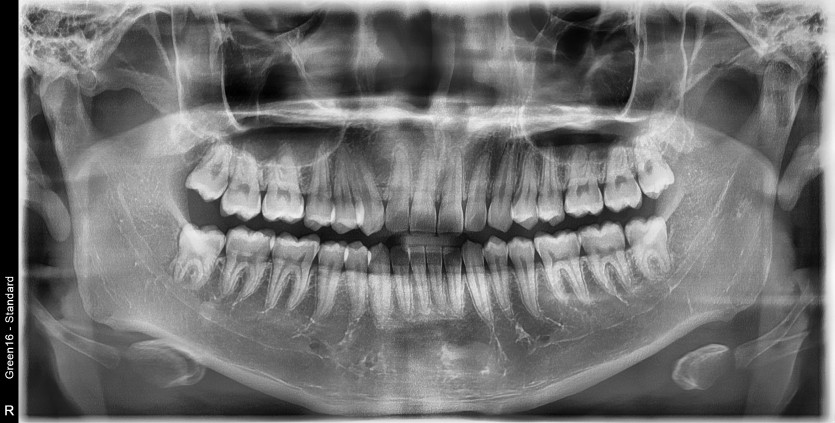

#28,38 사랑니 발치

구강 외과 전문의가 당일 발치했습니다.